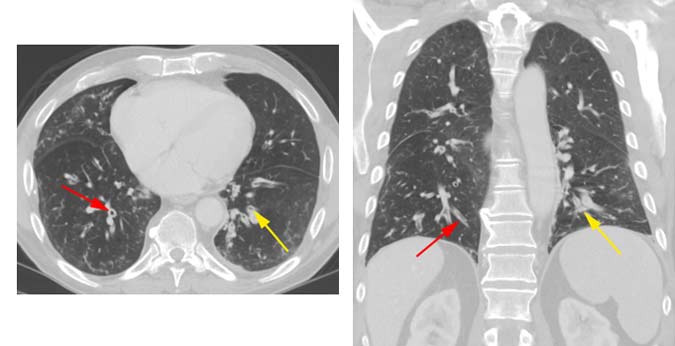

Exploración por tomografía computarizada (TC) en un paciente con bronquitis crónica mostrando engrosamiento de las paredes bronquiales (flechas rojas) y de la mucosa dentro del bronquio (flechas amarillas).

Nota: Las imágenes se muestra para fines ilustrativos. No trate de sacar conclusiones comparando esta imagen con otras en el sitio. Solamente los radiólogos calificados deben interpretar las imágenes.